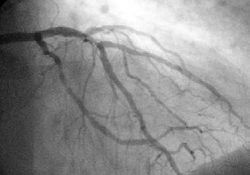

Angiography

In difficult cases or in situations where intervention to restore blood flow is appropriate, coronary angiography can be performed. A catheter is inserted into an artery (usually the femoral artery) and pushed to the vessels supplying the heart. A radio-opaque dye is administered through the catheter and a sequence of x-rays (fluoroscopy) is performed. Obstructed or narrowed arteries can be identified, and angioplasty applied as a therapeutic measure (see below). Angioplasty requires extensive skill, especially in emergency settings. It is performed by a physician trained in interventional cardiology.

Primary PCI involves performing a coronary angiogram to determine the anatomical location of the infarcting vessel, followed by balloon angioplasty (and frequently deployment of an intracoronary stent) of the thrombosed arterial segment. In some settings, an extraction catheter may be used to attempt to aspirate (remove) the thrombus prior to balloon angioplasty. While the use of intracoronary stents do not improve the short term outcomes in primary PCI, the use of stents is widespread because of the decreased rates of procedures to treat restenosis compared to balloon angioplasty.